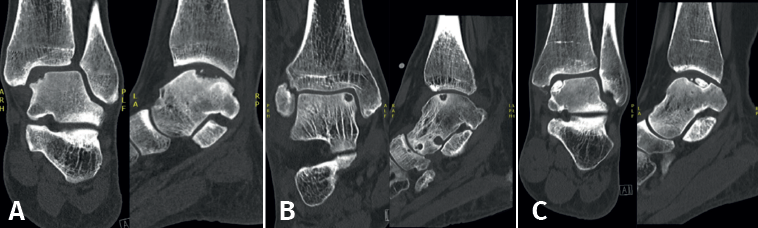

Lesions can be characterized by location, morphology, and size. Location can be described using a 9-grid anatomical scheme of the talus, as described by Raikin et al., shown in Figure 1(14). The morphology of OLTs can be described as crater-like, cystic, or fragmentary (Figure 2)(4,15,16). Lesion size should be reported in anterior-posterior plane, medial-lateral plane, and depth, allowing for calculation of lesion surface area and volume(4). However, there is no consensus on the reporting on morphology of OLTs, and while radiological classification systems for OLTs exist, they lack validation and utilize inconsistent terminology. Moreover, lesion size measurement methods vary, further contributing to inconsistency in lesion characterization in literature(15).

As an additional procedure, the debrided cyst can be filled with cancellous bone, particularly for large lesions, since the insufficient stem cells in the subchondral bone in these cases lead to a lower likelihood of adequate regeneration of damaged cartilage and subchondral bone(22,38). For primary OLTs, retrograde drilling has a success rate between 68% and 100% and a complication rate of 5%(22,29).

The post-operative protocol after retrograde drilling typically consists of 6 weeks of partial weight-bearing, allowing full range of motion immediately. Full weight-bearing is allowed after 6 weeks.